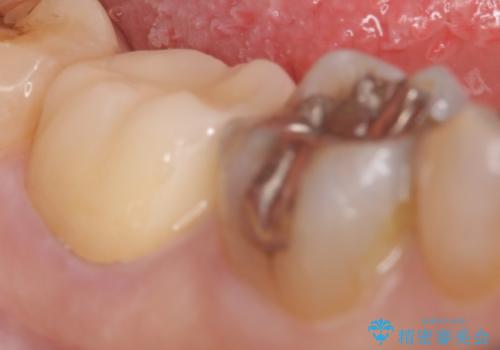

- 右下7の銀歯が外れてしまった方の症例です。

古い樹脂やカリエスを除去後、形を整え、オールセラミッククラウンによる補綴を行いました。